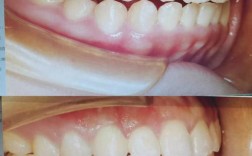

牙齿矫正是否可以只针对上牙进行,是很多存在牙齿问题者常有的疑问,正畸治疗并非必须上下颌同时进行,是否存在“只矫正上牙”的可行性,需结合牙齿问题的具体类型、咬合关系、颌骨发育情况等多维度因素综合判断,本文将围绕“牙齿矫正只矫正上面”的适用情况...